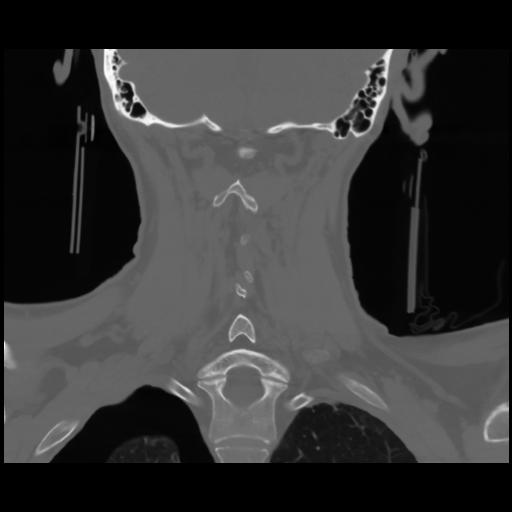

13 P.BLANDAS,,Coronal,2.000,P.BLANDAS,Coronal,